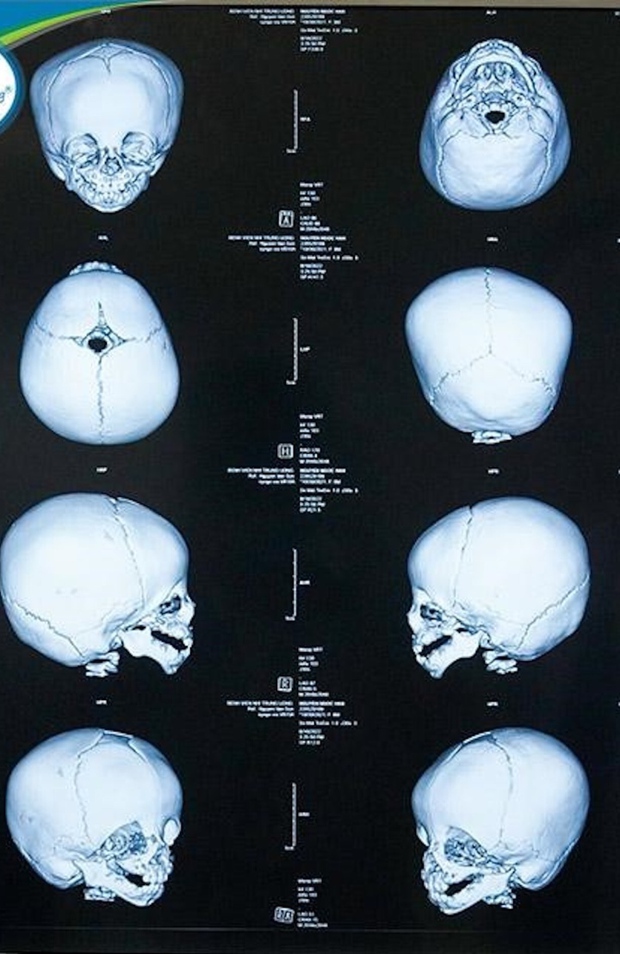

Bé N.H bị khuyết hai tai, biến dạng mắt, thiểu sản xương hàm dưới, thiểu sản xương hàm trên, khe hở vòm họng, dị tật khuyết xương gò má hai bên. Bé vừa được các bác sĩ khoa Sọ mặt và Tạo hình - Bệnh viện Nhi Trung ương xây dựng lộ trình điều trị và tạo hình lại vùng mắt bị khiếm khuyết, đưa hai mắt của trẻ trở lại vị trí sinh lý bình thường.

Bác sĩ Đặng Hoàng Thơm - Trưởng khoa Sọ mặt và Tạo hình, Bệnh viện Nhi Trung ương cho biết, bé N.H mắc hội chứng Treacher Collins, gây ảnh hưởng đến sự phát triển của xương và mô trên mặt, khiến bé N.H bị biến dạng nặng vùng sọ mặt. May mắn là não bộ của trẻ không bị ảnh hưởng.

Sau khi tiến hành khám và hội chẩn đa chuyên khoa, các bác sĩ xác định tình trạng bệnh của trẻ là một trường hợp khó, dị tật sọ mặt rất phức tạp, ảnh hưởng nghiêm trọng đến chất lượng cuộc sống và tương lai của bé, cần lên kế hoạch phẫu thuật kỹ lưỡng theo lộ trình phù hợp với tình trạng bệnh và độ tuổi của trẻ.

Bác sĩ Đặng Hoàng Thơm - người trực tiếp phẫu thuật cho bé N.H cho hay: “Tại vùng mắt, trẻ có khe hở số 6, 8 về xương, dây chằng góc mắt ngoài bị khuyết, góc mắt ngoài hai bên bị thấp hơn so với vị trí sinh lý bình thường, thiếu tổ chức cơ phần mềm mi dưới, gây tình trạng trễ mi, thường xuyên chảy nước mắt, góc nhìn bị hạn chế. Nếu không phẫu thuật, can thiệp sớm sẽ ảnh hưởng đến thị lực và thẩm mỹ của trẻ”.

Sau ca phẫu thuật kéo dài gần 2 giờ đồng hồ, bé N.H đã được các bác sĩ tái tạo lại dây chằng góc mắt ngoài hai bên, chuyển vị trí góc mắt ngoài về vị trí sinh lý bình thường (vị trí nằm ngang thay vì trễ xuống dưới như bệnh lý của bé). Các bác sĩ cũng tiến hành bù đắp tổn khuyết da và cơ vùng mi dưới bằng chuyển vạt da cơ lấy từ vùng mi trên, đóng khe xương hở và tạo hình sàn ổ mắt hai bên.